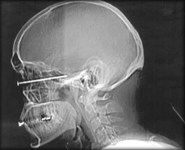

Stoopid: Uh...Ouch? -- Chris @ 3:48pm

How did this happen? I know this had to have hurt just a tad

Thanks to FARK for the picture.

All I can say is people and nail guns don't go well together.